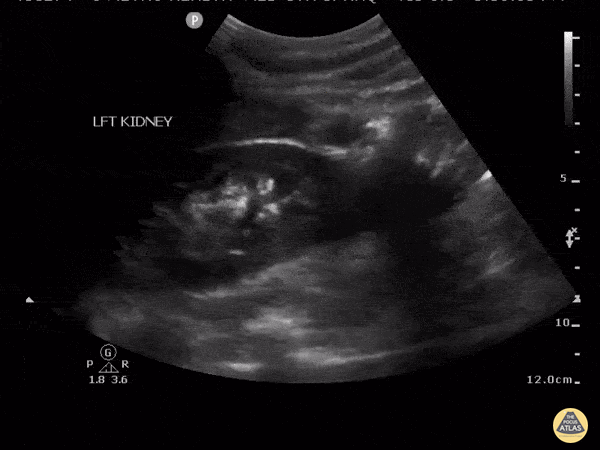

This clip demonstrates a renal abscess seen along the inferior pole of the kidney. Notice the circular shape with internal echoes and a hyperechoic rim demonstrated in both long and short axis. Image courtesy of Robert Jones DO, FACEP @RJonesSonoEM Director, Emergency Ultrasound; MetroHealth Medical Center; Professor, Case Western Reserve Medical School, Cleveland, OH View his original post here